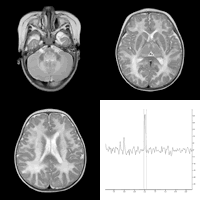

患儿女,8个月,智力发育落后,头大,尿N-乙酰天门冬氨酸(NAA)升高。MRI表现为双侧大脑半球脑白质对称性、弥漫性T2WI高信号,内囊、脑干、丘脑、苍白球、齿状核受累。1H 磁共振波谱分析(MRS)表现为NAA峰值明显升高,诊断为Canavan病。

图1~3 为MRI T2WI,显示双侧大脑半球脑白质对称性,弥漫性T2WI高信号,内囊、脑干、丘脑、苍白球、齿状核受累。

图4 为1H MRS,表现为NAA峰值明显升高。, http://www.100md.com